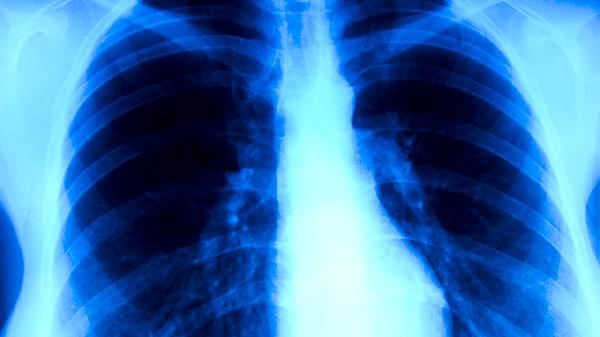

服用抗結(jié)核藥物后出現(xiàn)紅色尿液可能與利福平等藥物代謝產(chǎn)物有關(guān),也可能是泌尿系統(tǒng)出血的表現(xiàn)。主要影響因素有藥物代謝、尿路感染、腎結(jié)石、藥物性腎損傷、泌尿系統(tǒng)腫瘤等。建議立即就醫(yī)檢查尿常規(guī)和泌尿系統(tǒng)超聲,排除病理性因素。